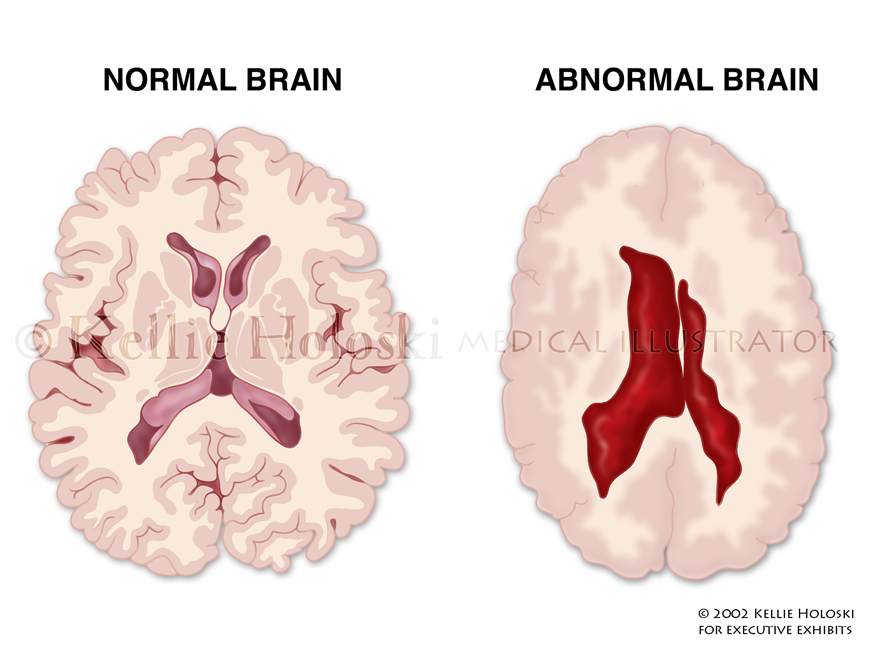

Abnormal Ventricles,

Adobe Photoshop

Courtroom exhibit for Executive Exhibits;

©Kellie Holoski -